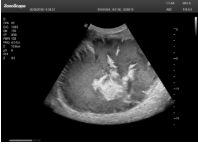

4容積探頭

積探頭是在二維圖像的基礎(chǔ)上,將連續(xù)采集的空間分布位置,經(jīng)過(guò)計(jì)算機(jī)重建算法,從而獲得完整的空間形態(tài)。

適用于:胎兒面部、脊柱和肢體等。

優(yōu)勢(shì)特點(diǎn):快速獲取、掃查連續(xù)均勻、解剖結(jié)構(gòu)顯示為容積數(shù)據(jù)、準(zhǔn)確進(jìn)行容積測(cè)量。